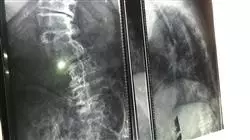

1.4.3. Técnicas de imagen: radiología simple, ecografía musculoesquelética, otros estudios de imagen